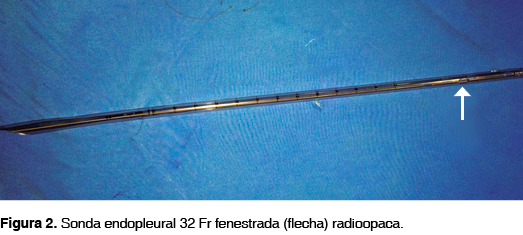

En todos los pacientes se emplearon sondas Argyle™ Thoracic Catheter Straight 32 Fr (10.7 mm) x 20" (51 cm) (figura 2), las cuales fueron colocadas entre las líneas axilar anterior y media en el quinto espacio intercostal (figuras 3 y 4), fijadas con seda 1 a la piel (figura 5) y conectadas a un sistema de drenaje torácico de tres cámaras Atrium™ Ocean Water Seal Chest 2002 Single Collection (figura 6) con succión continua a 20 cmH2O. Durante el procedimiento se les administró tramadol 100 mg por vía intravenosa e infiltró en el sitio de colocación con lidocaína al 2% con epinefrina a una dosis de 7 mg/kg, después se les proporcionó antibioticoterapia con ceftriaxona 1 g cada 12 horas por vía intravenosa durante el período de permanencia de la sonda y analgesia con ibuprofeno 400 mg cada ocho horas por vía enteral si estaba disponible la misma, hasta el retiro de la sonda; además, recibieron curación diaria del sitio de inserción de la sonda -consistente en lavado del sitio quirúrgico con iodopovidona y movilización gentil de la sonda, verificando su permeabilidad- bajo analgesia con tramadol y con posterior control radiográfico.

Para la elección del tamaño apropiado de una sonda endopleural se considera que su diámetro, y en menor medida su longitud, son los determinantes más importantes de la velocidad de flujo en su interior; sin embargo, es necesario tomar en cuenta qué clase de material es el que se desea drenar y la velocidad con la cual se genera. En este sentido y para fines prácticos, puede afirmarse que la producción continua y rápida de líquidos viscosos, como la sangre, amerita el empleo de sondas de mayor diámetro que las que se utilizarían para drenar un volumen similar de aire.7,8,12 Tradicionalmente, en el Hospital Central de la Cruz Roja Mexicana se han utilizado sondas de calibre 32 Fr, pues es un tamaño cómodo para evacuar neumotórax, hemotórax y hemoneumotórax traumáticos.